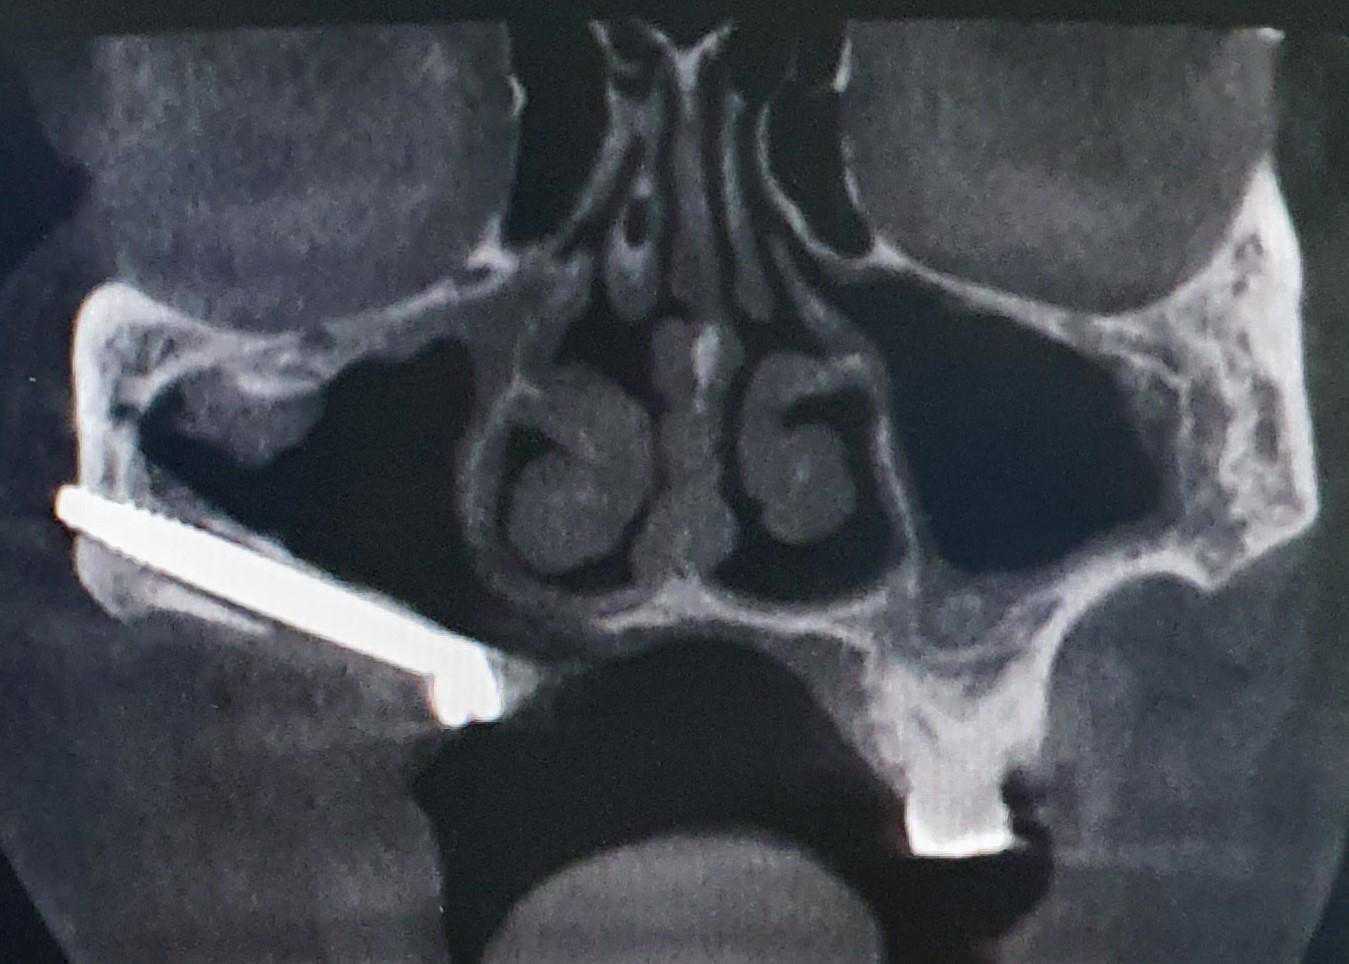

https://demo.discussdentistry.com/forums/topic/post-mucormycosis-avascular-necrosis-of-maxilla-rehabilitation-with-zygomatic/#post-24499 <![CDATA[Post Mucormycosis Avascular necrosis of maxilla, rehabilitation with Zygomatic]]> https://demo.discussdentistry.com/forums/topic/post-mucormycosis-avascular-necrosis-of-maxilla-rehabilitation-with-zygomatic/#post-24499 Thu, 25 Aug 2022 12:14:40 +0000 Sankalp Mittal

• 20210604_101325 (2)20210604_101317 (2)20210604_103315 (2)20210604_102857 (2)20210604_104202 (2)20210604_104853 (2)20210824_105656 (2)20210824_112353 (2)20210824_114957 (2)20210824_131302 (2)20210826_100648 (2)20210826_100749 (2)20210826_100919 (2)20210914_183943 (2)20211001_17535220211012_18543620211012_192043 (2)20211012_185627 (2)20211012_195430 (3)20211027_193725 (2)20211027_200729 (2)20211027_200919